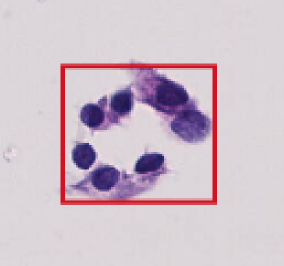

Identify Pattern

1. Benign follicular nodule

2. Undetermined follicular disease

3. Suspicious for follicular tumor

4. Suspicious for malignancy tumor

5. Papillary thyroid carcinoma